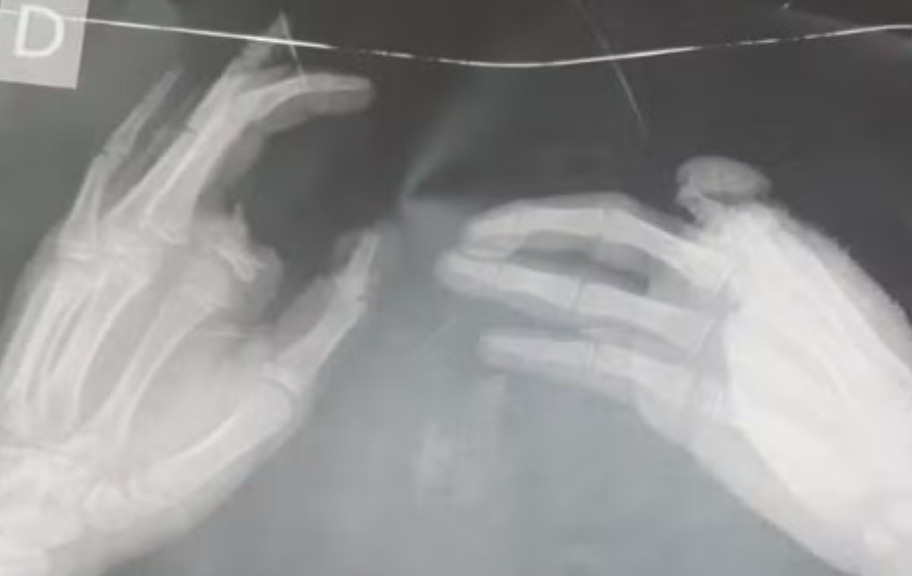

A criança foi atendida pelo Samu, levado ao hospital, e submetido a uma cirurgia na última quinta-feira (12). Os estilhaços também atingiram outras partes do corpo, como o pescoço, o rosto e o tronco da criança.